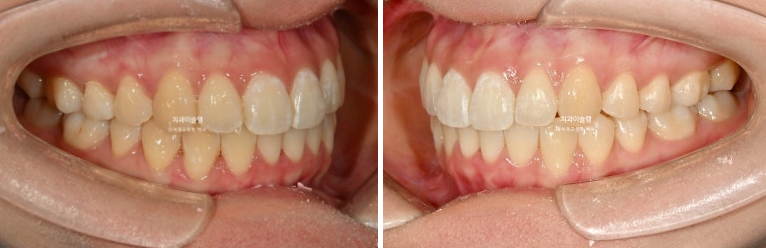

개선된 덧니와 가위교합

24.02~25.10